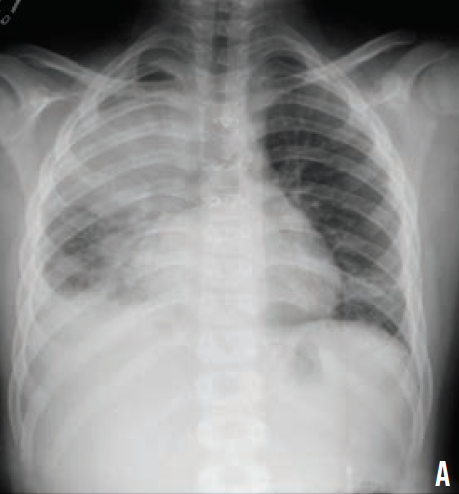

On admission, his white blood cell count was 39,000/µL, and his and C-reactive protein level was 29.3 mg/L. A chest radiograph revealed a right upper lobe consolidation (A). He was started on cefuroxime and nebulized albuterol.

Because of his worsening leukocytosis and respiratory status, he was transferred to the intensive care unit. An infectious disease specialist was consulted, and laboratory studies for various viruses and bacteria were ordered. Vancomycin and meropenem were started. Due to progressive respiratory distress and eventual respiratory failure, the patient was intubated. A computed tomography scan of the chest showed necrotizing right lung pneumonia with diffuse pneumonitis (B). Urine cultures were positive Legionella pneumophila, and he was started on intravenous azithromycin.